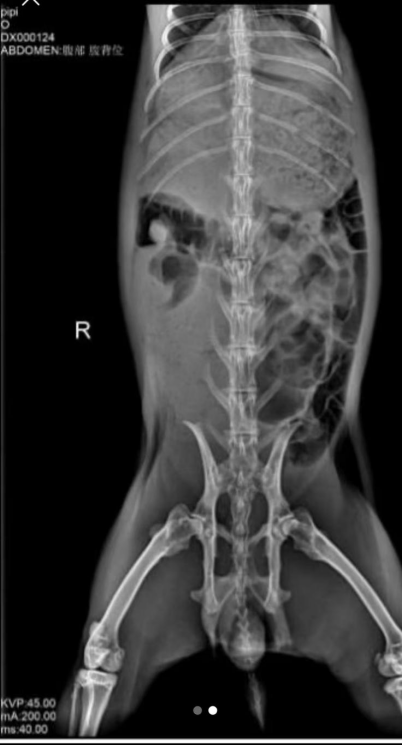

X-ray imaging revealed severe cecal bloating and food accumulation in the stomach. We advised the owner to be cautious when reviewing the images, as they could be unsettling.